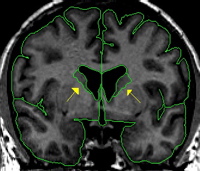

|  | The caudate is a C-shaped structure with an enlarged head deep in the frontal lobe and an increasingly attenuated body and tail which follow the lateral ventricle around into the temporal lobe. We do not consider the tail of the caudate in the CMA method. In the coronal view the caudate appears lateral to the lateral ventricles in each hemisphere. The caudate begins very small and reaches its largest extent in the early to mid region and grows smaller as you travel more posterior until it finally disappears. The caudate is bordered inferiorly by white matter, the thalamus (when present), or the nucleus accumbens (when present). The caudate is bordered superiorly by the transverse fibers, or white matter. Laterally, the caudate is bordered by white matter. The medial border is the lateral ventricle. |

Anteriorly, there is some partial voluming, so care should be taken not to overestimate the caudate. Projection lines should be used to determine the true extent of the caudate | |